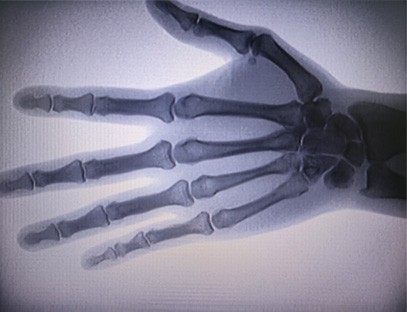

Преносимият рентгенов апарат As-c200 е преносим инструмент с малка доза радиация и много безопасен. Особено подходящ е за звена и лица с недостатъчен бюджет и ниски изисквания към снимките. Новото поколение е оборудвано с 10-инчов голям екран с висока разделителна способност, който има по-голям диапазон на перспектива и може да изгледа изцяло цялата длан. Подходящ е най-вече за медицинска ортопедична гледна точка. Може да се свърже с филмов принтер за отпечатване на ортопедични фолиа, а също така може да се използва в промишлено производство и тестване. Без тъмна стая, директна перспектива, незабавно наблюдение, висока разделителна способност и ясно изображение.

Нашият ортопедичен рентгенов апарат е висококачествен продукт, който е проектиран специално за ортопедични изображения. Може да се използва за диагностика и планиране на лечение на различни ортопедични състояния, включително фрактури, луксации, артрит и костни тумори. Той е оборудван с усъвършенствана рентгенова технология, която позволява висококачествени изображения с намалено излагане на радиация. Машината има система за изображения с висока разделителна способност и може да заснема изображения на всяка костна структура с голяма яснота.

3. Голям дисплей с изображения: Машината разполага с голям дисплей с изображения, осигуряващ ефективен работен процес и лесно идентифициране на критични констатации.